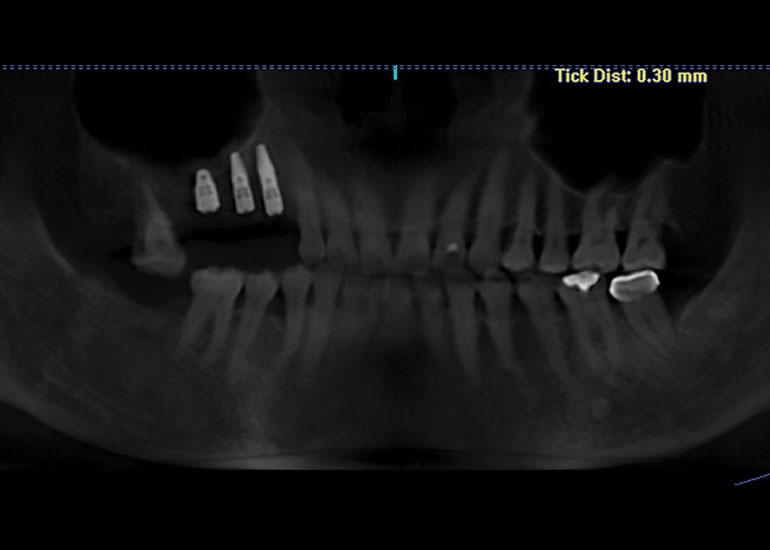

Recently, I placed three implants in Teeth 3, 4 and 5 in conjunction with a sinus lift. Implants in such close proximity to one another can be a challenge even for a specialist. By using the preplanning software, I virtually placed the implants precisely where I wanted them to go, as shown in Figs. 7, 8 and 9. I was thrilled with the outcome. As you can see on the X-ray in Fig. 10, the implants were placed precisely according to the plan.

Fig. 10: Final image showing implant placement and sinus lift.